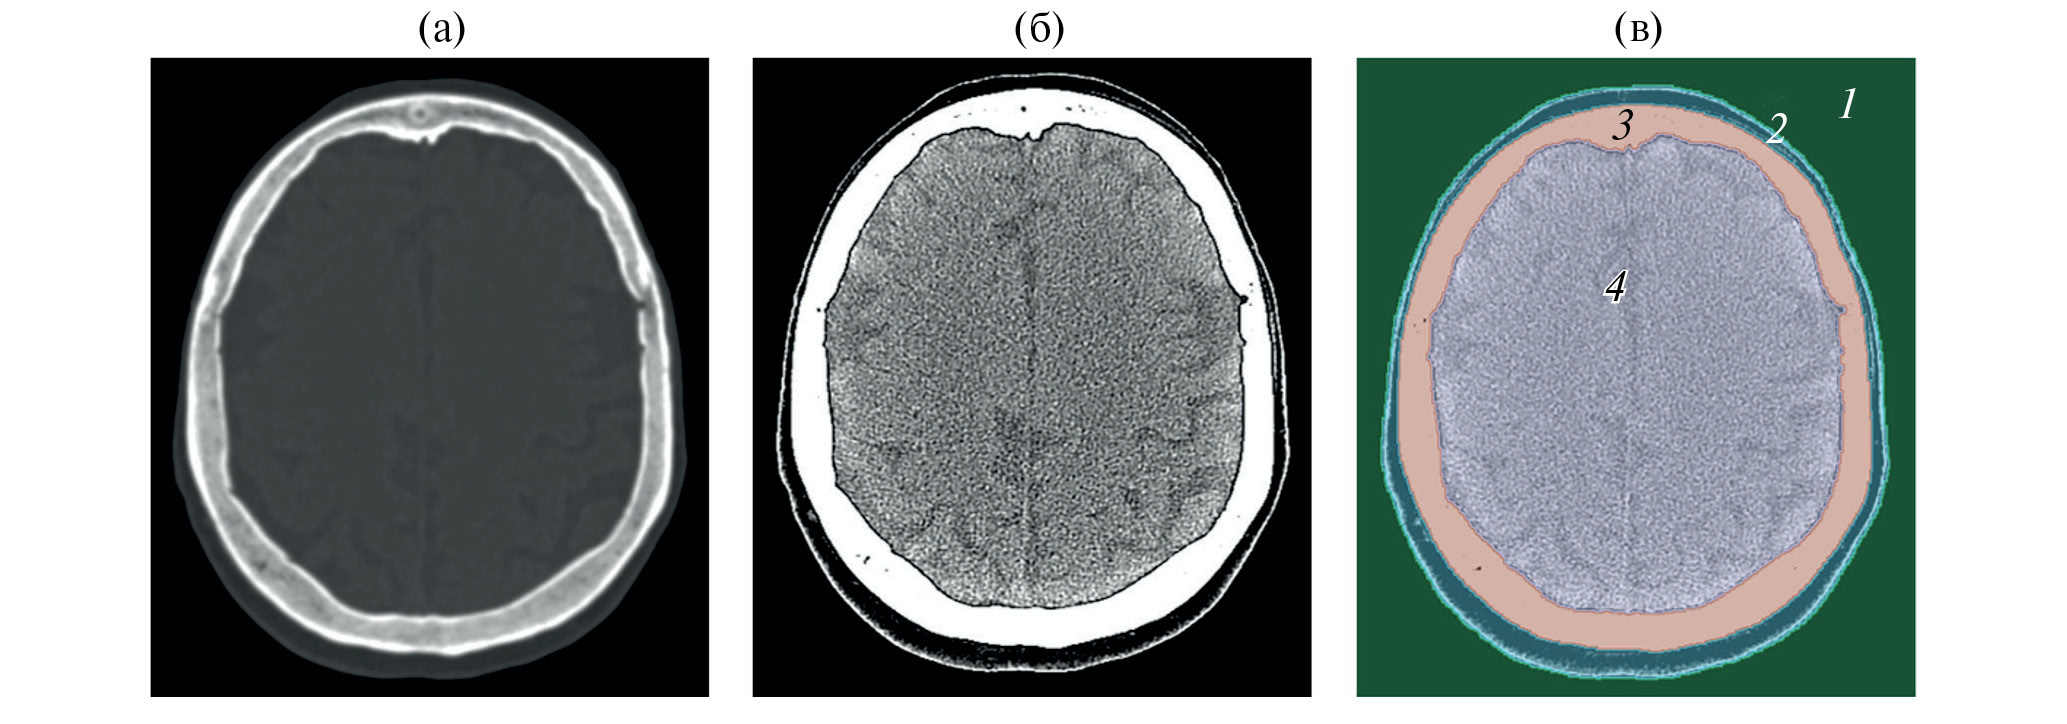

Данные МРТ представляли собой T1-взвешенное трехмерное изображение с набором из 176 аксиальных срезов с разрешением 1 × 1 × 1 мм. В отличие от КТ-изображения, МРТ предоставляет только качественную визуальную информацию о тканях и органах. Сегментация МРТ-изображения была проведена в два этапа. На первом этапе изображение сегментировалось в программе открытого доступа BrainSuit21a (brainsuite.org), однако из-за ограниченного разрешения МРТ-изображения и анатомических особенностей строения головы человека (наличия зрительных нервов и т.д.) выделение границ черепа с использованием детектора Марра–Хилдретта, используемого в программе BrainSuit21a, дает неточности [21, 22]. Поэтому, для более точного определения границ тканей, сегментация была доработана вручную в программе Slicer, ориентируясь на визуальные границы анатомических структур (рис. 2) [20].

Рис. 2. Аксиальный срез магнитно-резонансной томографии головы человека (а) – до сегментации; (б) – после сегментации в программе BrainSuit; (в) – после доработки в программе Slicer. Цвета сегментов соответствуют таковым на сегментации КТ.